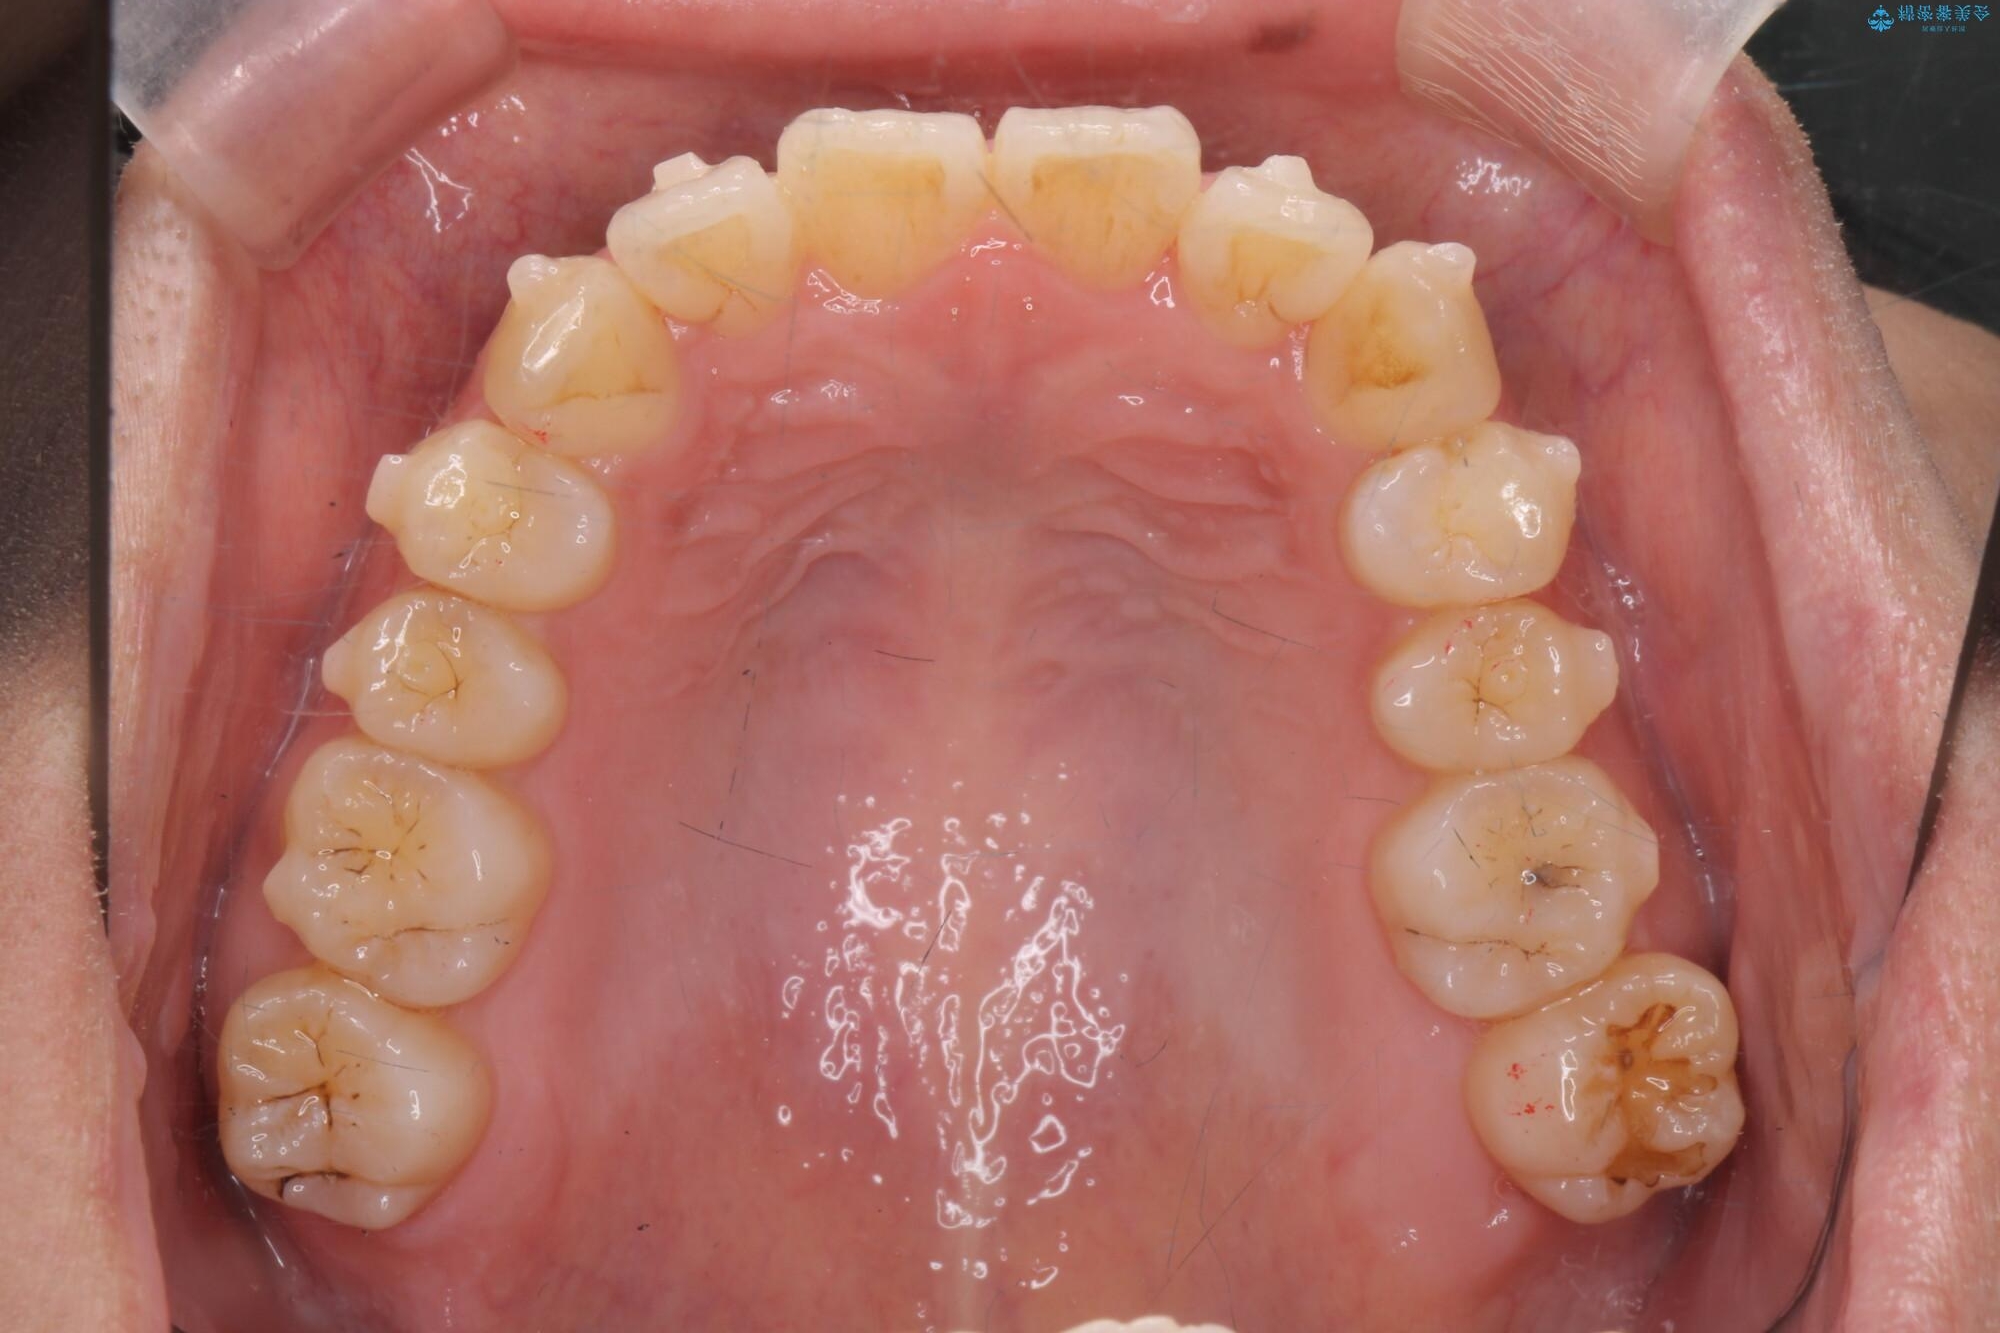

治療中

気になる犬歯のガタつきをマウスピース矯正で改善 治療中画像 気になる犬歯のガタつきをマウスピース矯正で改善 治療中画像 気になる犬歯のガタつきをマウスピース矯正で改善 治療中画像 気になる犬歯のガタつきをマウスピース矯正で改善 治療中画像